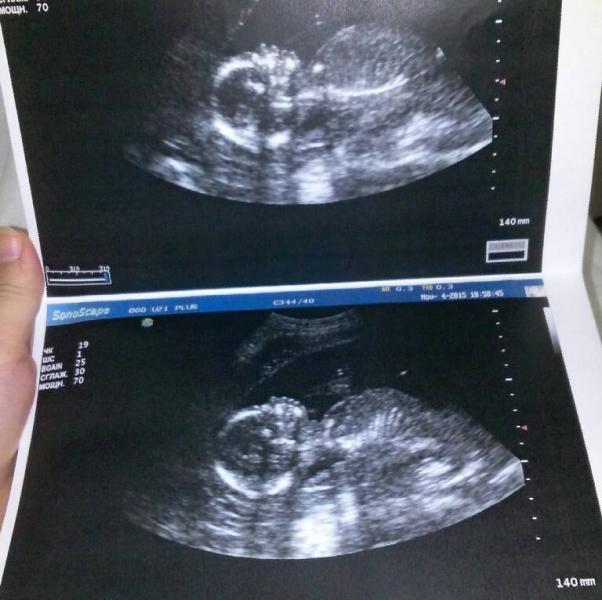

хочу поделиться своей радостью))) у нас девочка))) 250 г. ))) но вот, беда( тонус( в больничке лежим(

@mamochkavlada и вас тоже) а тонус, это да( УЗИ делала в "УЗИ+" рядом с Кавказом. могу скинуть данные) там хоть и молодая, но опытная и поднимающая девушка) берет не дорого, бесплатные фото) и сами видите какого качества)